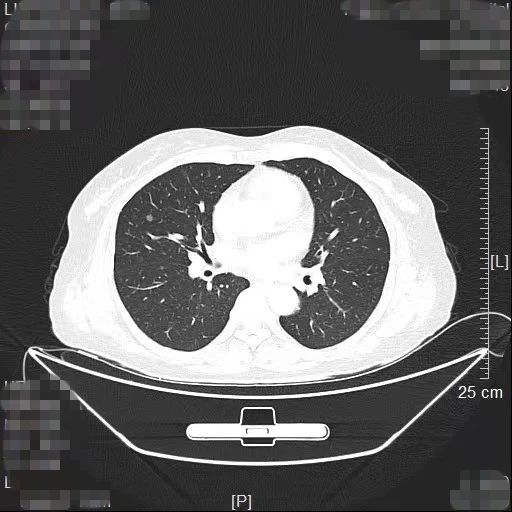

患者林女士今年65岁,长期旅居国外的她在回国后常规体检时查出右肺有2个高危的磨玻璃结节,慕名找到我院胸部肿瘤外科方卫民主任医师。医生团队详细分析了患者的肺部CT及三维重建结果,发现2个结节分别位于右上肺后段边缘及右中肺叶中央,如果直接采用手术切除的方法,要多切除整个右肺中叶,将损失较多的正常肺组织,影响生活质量,得不偿失。

三维重建结果

由于患者签证时间将到,无法分次手术,医生团队经过反复讨论,最终为患者量身定做了“针孔消融+单孔微创”的杂交手术方案。首先在医院肿瘤与血管微创介入治疗中心CT引导下为患者右中肺叶结节进行热消融治疗,仅仅一个针眼;接着进行单孔胸腔镜亚肺段切除,仅仅一个3cm大小的切口,术中冰冻病理报告:原位腺癌,疑有浸润。顺利为患者解除了肺部的2个健康隐患。